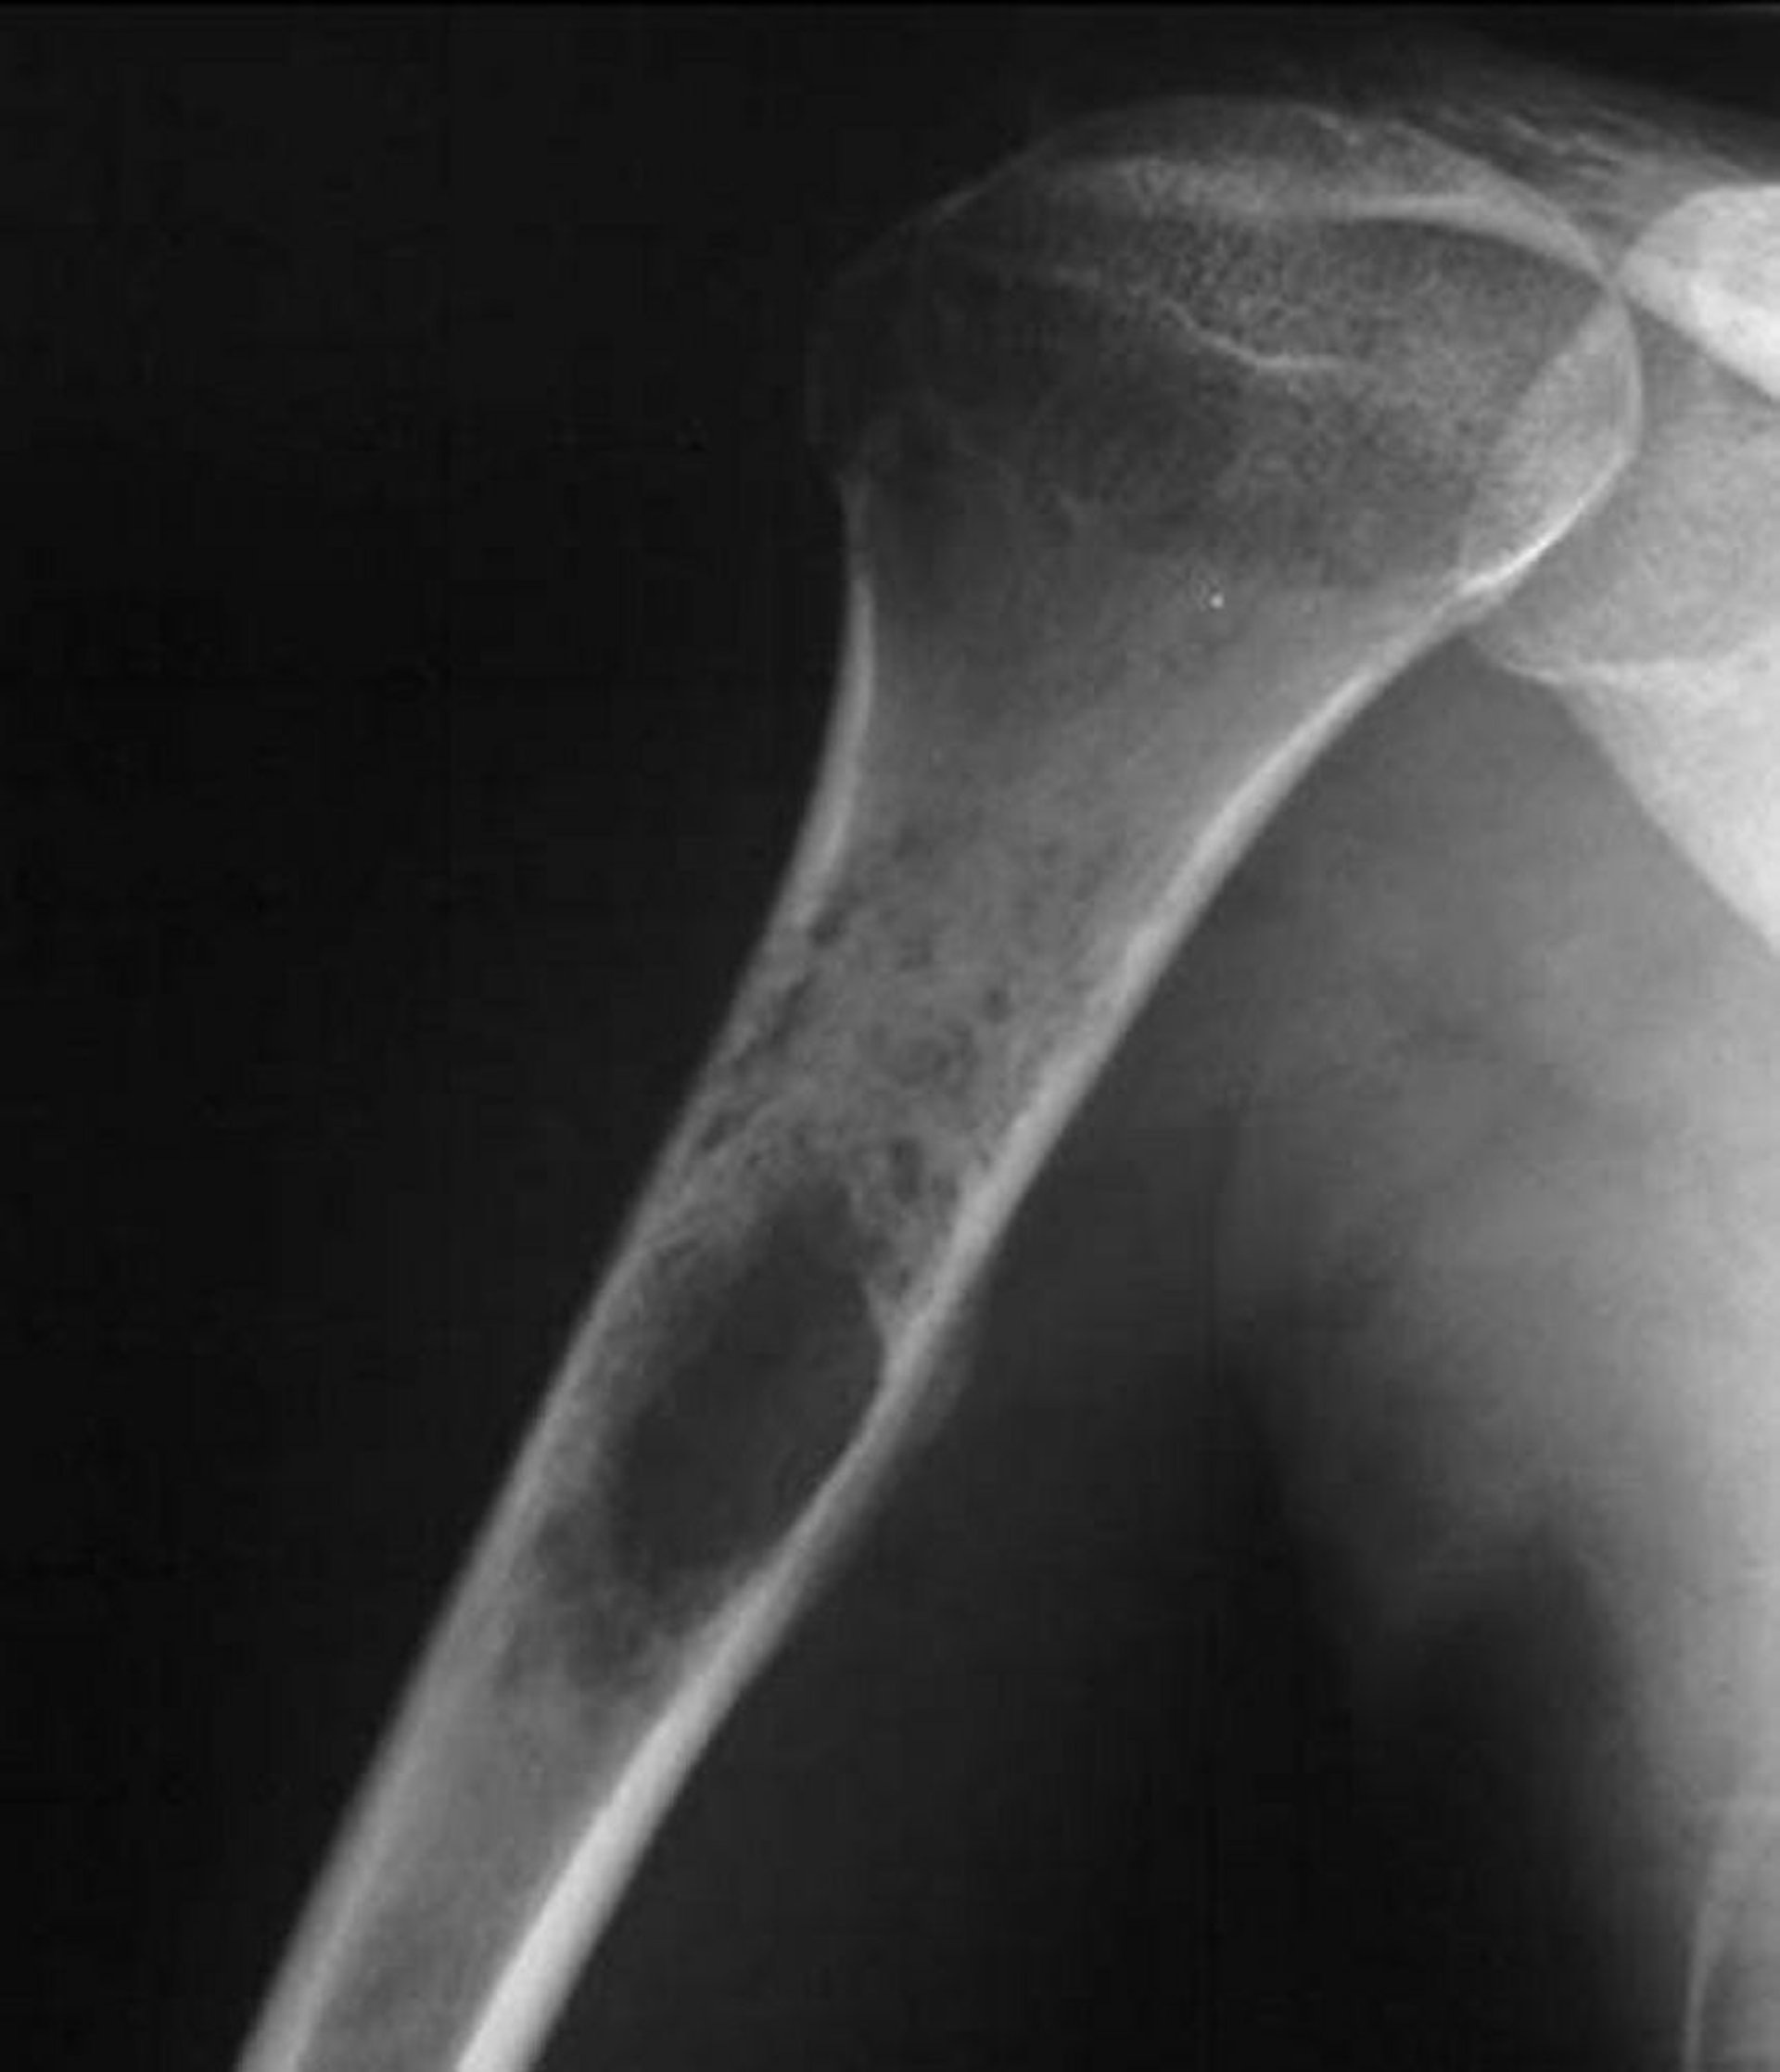

Остеосаркома Юинга

На данном рентгеновском снимке плеча показана пермеативная деструктивная опухоль, возникающая в проксимальном отделе плечевой кости, что характерно для саркомы Юинга.

Image courtesy of Michael J. Joyce, MD, and Hakan Ilaslan, MD.